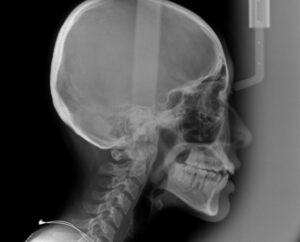

この歯並びの治療計画は

でっ歯さんの度合いを調べる

セファロというレントゲンを撮影